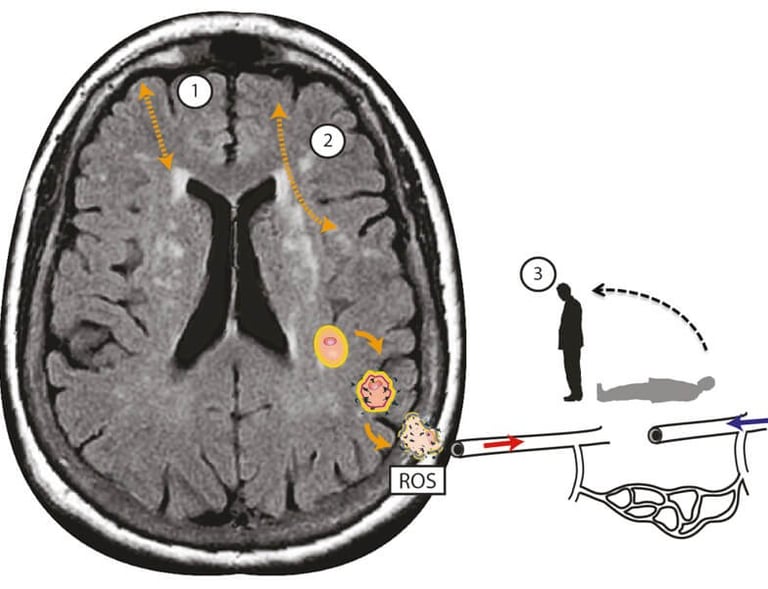

Şekil 1. Kortiko-subkortikal beyin küçük damar hastalığı ile ilişkili baş dönmesinde postüral kan basıncı hipotansiyonunun ek zararlı etkilerinin şematik gösterimi. (1) ve kortiko-kortikal (2) bağlantı kopukluğu. Lokalize oksidatif stres süreçleri serebral damarları hasarlandırarak endotel disfonksiyonuna yol açar ve reaktif oksijen türleri (ROS) yoluyla beyin dokusunda nörodejeneratif değişiklikleri teşvik eder. Mikrovasküler endotel disfonksiyonu ise serebral otoregülasyonu bozar; bu da sağlıklı durumlarda kan basıncı düştüğünde yeterli ve istikrarlı serebral kan akışını korur. Bu, postural baş dönmesi ve dengesizlik olarak kendini gösteren intra-serebral ortostatik hipotansiyon ve perfüzyona yol açar. Kaski ve ark. [4]'den Elsevier'in izniyle yeniden basılmıştır. Bu tür dağıtılmış fonksiyon, aynı anda birçok alanda birden fazla bağlantıyı etkileyen cSVD tarafından bozulma riski altındadır. Yaşla ilişkili serebral küçük damar hastalığının (cSVD) birikimiyle oluşan bağlantı kaybı, aşağıdaki mekanizmalardan bir veya daha fazlası aracılığıyla baş dönmesi hissine yol açabilir (bkz. Şekil 1): kortikal vestibüler merkezlerin bağlantısının kesilmesi, frontal yürüyüş merkezleri ile bazal gangliyonlar arasındaki bağlantının kesilmesi ve amaçlanan motor eylem (efference kopyası) ile yükselen duyusal girdiler (duyusal re-afféference) arasındaki bağlantının kesilmesi. Ek olarak, serebral kan basıncının cSVD aracılı düzensizliğinin ayakta durma ve yürüme sırasında baş dönmesiyle bağlantılı olduğunu ve bu hastalarda kollardaki postural kan basıncı ölçümünün genellikle normal olmasının nedenini açıkladığını öne sürüyoruz [4]. Şu anda, baş dönmesinin net bir nedeni olmadığı için, tedavi hastaların semptomlarını yönetmelerine ve genel olarak dengeyi iyileştirmek için fizyoterapiye odaklanmaktadır. Serebral küçük damar hastalığı ile bağlantı, bu hastalarda yaşa bağlı olarak aşırı beyaz madde hiperintensiteleri veya küçük damar hastalığının diğer belirteçlerinin kanıtlarını aramak için beyin MR'larının istenmesinin faydalı olabileceğini düşündürmektedir. Eğer mevcutsa, sigara, hipertansiyon ve diyabet gibi vasküler risk faktörleri araştırılmalı ve en uygun şekilde ele alınmalıdır. Kronik küçük damar hastalığında (cSVD) optimal kan basıncı, devam eden bir araştırma alanıdır (PROHIBIT-ICH) ve küçük damar hastalığını daha iyi hedefleyen yeni ilaçlar üzerine çalışmalar devam etmektedir (LACI-2).